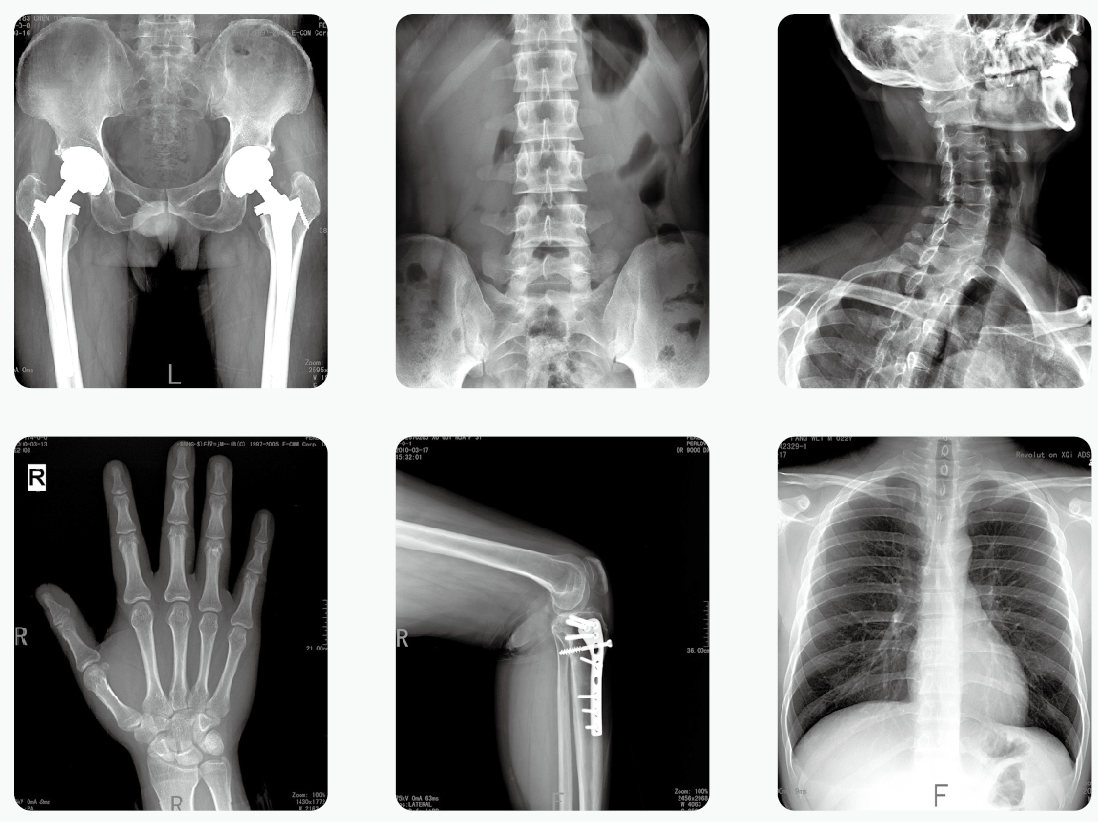

通過醫(yī)用X光機(jī)檢查,臨床醫(yī)生可以獲取病人很多重要的,甚至性命攸關(guān)的醫(yī)療信息,比如肺炎、骨折、腸梗阻等。這些普通X光檢查,對平常人而言就像是拍數(shù)碼照相,咔~可以了。但是對孕婦而言,有時(shí)的確是一個(gè)艱難的決策。那么,醫(yī)用X光機(jī)檢查,孕婦到底能不能做?

其實(shí),絕大部分醫(yī)用X光機(jī)檢查的部位都是四肢、頭、牙齒或者胸部,孕婦的生殖腺并沒有直接暴露在X光下。因此,在這些情況下,只要合理曝光及防護(hù),對胎兒是沒有危害和影響的。

但是,如果孕婦需要做腹部、盆腔、腰椎等醫(yī)用X光機(jī)檢查,此時(shí)胎兒是直接暴露在X光下的,這種情況就需要與醫(yī)生探討X光檢查的利弊后再做決定。